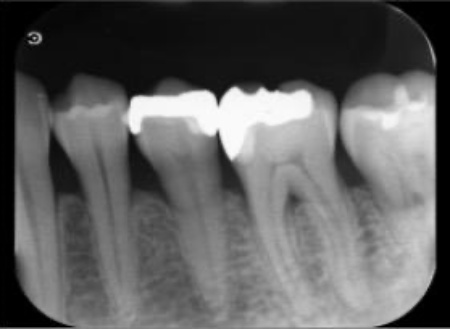

レントゲンを撮影して詳しく調べたところ、歯の奥側の根の先端部分に骨が溶けたことで黒く透けて見える透過像が確認されました。

この透過像は歯の神経や血管が通る管「根管」の内部で細菌感染が起こり、根の先にまで炎症が広がっているサインです。

その後、清掃した根管内に薬剤を充填し根管内を密閉する根管充填を施しました。

今回使用する薬剤は、生体親和性が高く封鎖性にも優れたMTAセメントを採用しています。

最後に、治療後のレントゲンで4本すべての根管に充填材が緊密に行き渡っていること、処置部位に問題がないことを確認して、治療を終了しました。